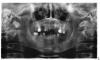

_Marina_ Опубликовано 3 августа, 2013 Поделиться Опубликовано 3 августа, 2013 Здравствуйте.Проконсультируйте меня, пожалуйста. Подлежат ли все имеющиеся зубы удалению с последующим полным протезированием на имплантах или что-то можно полечить? Верхние 6, 7 слева и нижняя 5 справа выдвинулись из-за длительного отсутствия антагонистов. Верхняя 7 справа мигрировала вбок. Если эта инфо имеет значение для оценки перспектив сохранения зубов (ну вдруг , то справочно: многие родственники по линии одного из родителей полностью теряли зубы к 20-30 годам, мне 33 года. Причина: кариес дентина. Посещения стоматологов с выполнением предписаний видимым образом не приостанавливали процесс разрушения. Это уже потеряло оттенок трагичности, сколь незыблемо и как-то даже традиционно что ли сыпятся мои зубки Снимок прилагаю.Буду благодарна, если уделите внимание моему вопросу. Ссылка на комментарий

Bier Опубликовано 4 августа, 2013 Поделиться Опубликовано 4 августа, 2013 Плохого качества снимок. Еще бы фотографии увидеть Ссылка на комментарий

_Marina_ Опубликовано 4 августа, 2013 Автор Поделиться Опубликовано 4 августа, 2013 Фото прилагаю. На предыдущем панорамном снимке еще фигурируют удаленные в течение прошедшего месяца:Справа на в.ч. – 8Справа на н.ч – 6, 7 (случился первый в жизни флюс) Ссылка на комментарий

Bier Опубликовано 4 августа, 2013 Поделиться Опубликовано 4 августа, 2013 Пожалуй нужно вести речь о тотальном удалении и имплантации, часть зубов можно сохранять как временные опоры для временного протезирования. 1 Ссылка на комментарий